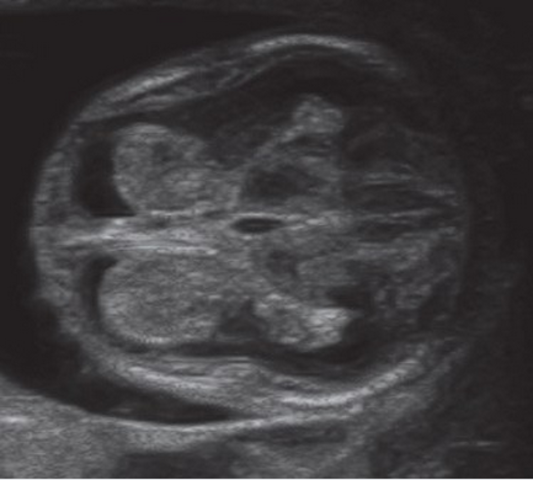

Formación de vesículas primarias

Los movimientos del tubo neural evidencian los precursores de las regiones encefálicas principales; a los 28 días de desarrollo, el tubo neural cierra y el neuroporo rostral se divide en tres cámaras interconectadas (ventrículos). El tejido alrededor de los ventrículos da origen a tres vesículas primarias, bases del encéfalo (prosencéfalo, mesencéfalo y rombencéfalo), las cuales cuentan con sus respectivas subdivisiones.